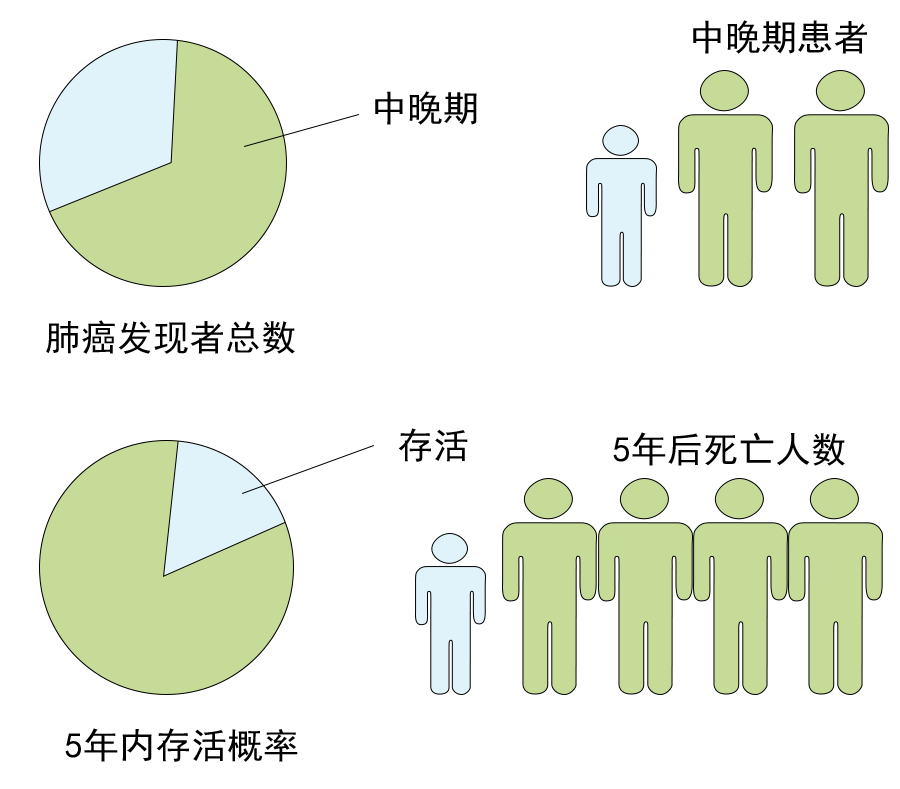

肺癌是如何分期的,治愈率怎么样的?

肺癌是如何分期的,治愈率怎么样的?

小细胞肺癌与非小细胞肺癌介绍,生存期怎么样?...

小细胞肺癌与非小细胞肺癌介绍,生存期怎么样?...